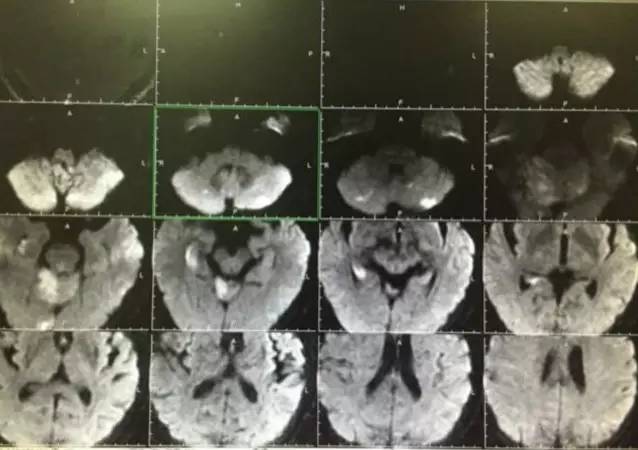

▼术后复查头颅MRI显示小脑蚓部及小脑半球有散在的梗死灶,脑干未见梗死。头颅MRA显示后循环血管通畅。